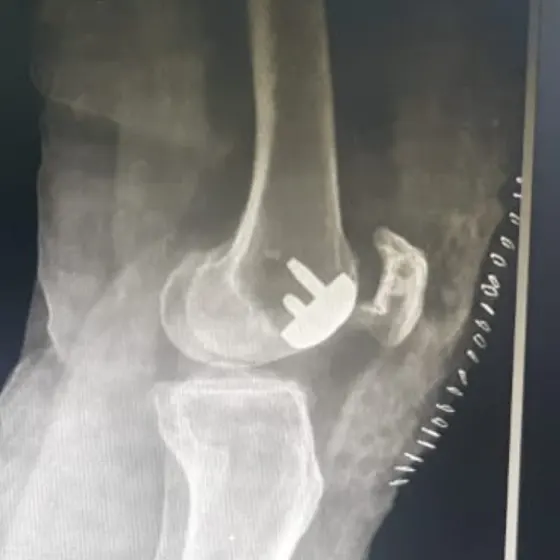

Episurf trochlear patellar replacement

Advance Hospitals, Ahmedabad Becomes the First in the Region to Perform Patient-Specific Patello-Femoral Replacement Using the Episurf Technique

Ahmedabad, July 2025 — In a groundbreaking achievement, Advance Hospitals, Ahmedabad has become the first center in the region to perform patient-specific patello-femoral replacement using the Episurf technique, a revolutionary approach in joint preservation and early knee arthritis management.

The surgery was successfully performed by Dr. Prathmesh Jain, a leading arthroscopy and joint preservation surgeon and Director of Advance Hospitals. Known for his innovations in cartilage and ligament surgery, Dr. Jain has once again positioned the hospital at the forefront of orthopedic excellence.

The Episurf technology involves custom-made implants designed for each patient based on 3D MRI analysis, ensuring precision fit, minimal bone loss, and faster recovery. This technique is particularly beneficial for younger patients with isolated patellar or trochlear cartilage damage who are not ideal candidates for total knee replacement.

“This is a game-changer for young patients with early patello-femoral arthritis or cartilage injuries. With Episurf, we are able to treat the damaged area precisely without compromising healthy bone and joint structure,” said Dr. Prathmesh Jain.

Advance Hospitals continues to lead in innovation by offering world-class surgical solutions for cartilage repair, meniscus preservation, ACL reconstruction, and now, customized knee resurfacing with Episurf—providing patients a new lease on active life.